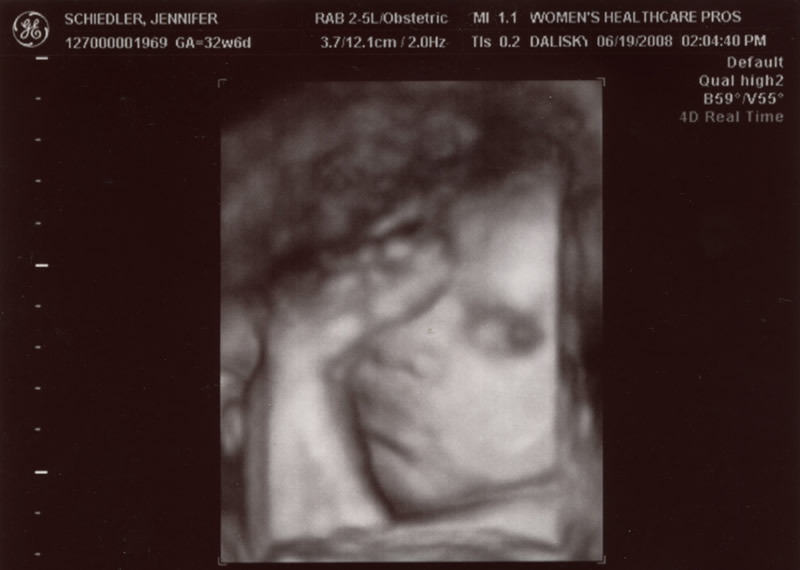

| June 19, 2008 |

Had my 32 week check up today. Baby is measuring 2 1/2 weeks

ahead and Dr Dalisky is predicting a 9 pound baby. Yikes am I

excited! We got a pic of his face. Baby is holding his foot up

by his face. Much more flexbible then we are. We saw his heart

beating, his spine & bladder. My BP was normal.....totally

shocked me. I only gained one pound. Yay! I'm 9 pounds lighter

then this time with Greyson even though I think I look bigger.

We are still holding to the 8/8/08 due date. Any bets on when

he'll make his appearence?!